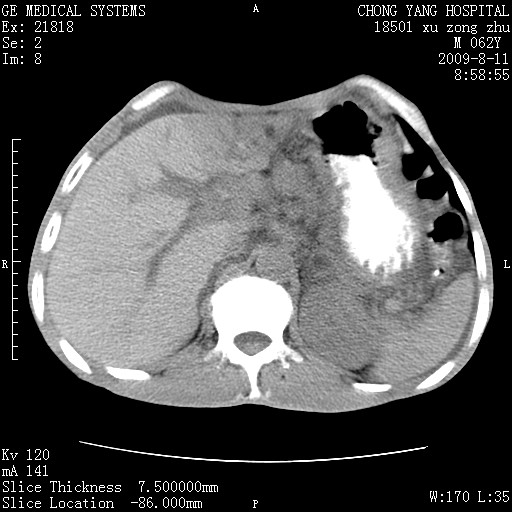

以下是引用杀毒软件在2009-8-11 16:35:00的发言:[br]肝内胆管扩张局限于左叶,胆管内有结石伴肝外胆管结石,胆管壁增厚呈弥漫性并发腹腔积液,胰腺边界模糊。[br][br]考虑---胆总管及肝内胆管结石继发胆管炎及胰腺炎,左肾下极囊肿,腹水。

以下是引用zjzjr在2009-8-11 17:35:00的发言:[br]肝内胆管扩张局限于左叶,胆管内有结石伴肝外胆管结石,胆管壁增厚呈弥漫性并发腹腔积液。[br][br]考虑---胆总管及肝内胆管结石继发胆管炎,左肾下极囊肿,腹水。